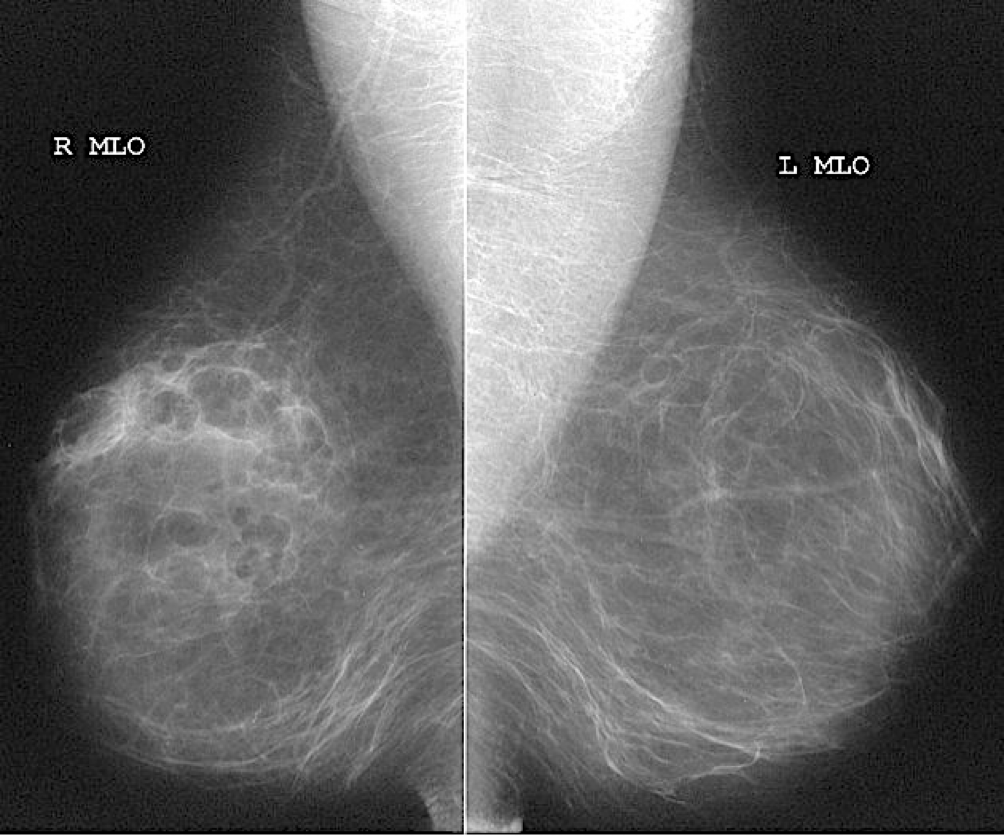

Routine diagnostic mammography projections

- Craniocaudal (CC)

- Medio lateral oblique (MLO)

Mammography findings of benign and malignant breast lesions #Z

| Benign lesion | Malignant lesion | |

|---|---|---|

| Appearance of the lesion | - •Well-defined, circumscribed mass | - •Focal mass or density |

| Margins z | - •Surrounding radiolucent ring (halo sign) | - •Poorly defined, spiculated margins |